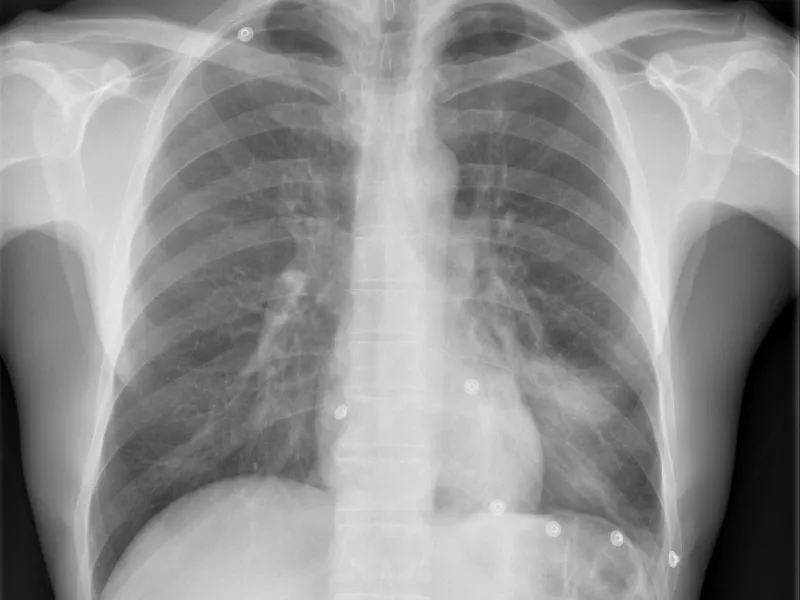

La radiografía de columna sigue siendo uno de los estudios más solicitados en la práctica médica cotidiana. Es una herramienta simple, accesible y de enorme valor diagnóstico tanto en urgencias como en la consulta ambulatoria.

Continúa siendo el primer paso en el algoritmo diagnóstico en el paciente con dolor de columna, traumático o no. La radiografía de columna permite detectar principalmente alteraciones óseas, degenerativas o traumáticas, y muchas veces orienta la conducta inicial del médico antes de recurrir a estudios más complejos.

Antes de comenzar a interpretar una radiografía, debemos asegurarnos de que la imagen sea de buena calidad, para evitar los errores diagnósticos.

Para evaluar cualquier segmento de la columna es de buena práctica obtener al menos dos proyecciones ortogonales del segmento de interés:

- Anteroposterior (AP o frontal)

- Lateral o de perfil

Si fuera necesario, pueden agregarse incidencias oblicuas, transorales (en la columna cervical) o dinámicas (flexo-extensión).

1.2 Calidad técnica

Un error técnico puede confundirte y ser causa de errores diagnósticos. Antes de diagnosticar, verifica siempre la calidad de la proyección.

Una buena radiografía debe permitir visualizar todos los segmentos del área estudiada:

- En la columna dorsal, todo el segmento torácico visible entre las clavículas y el diafragma.